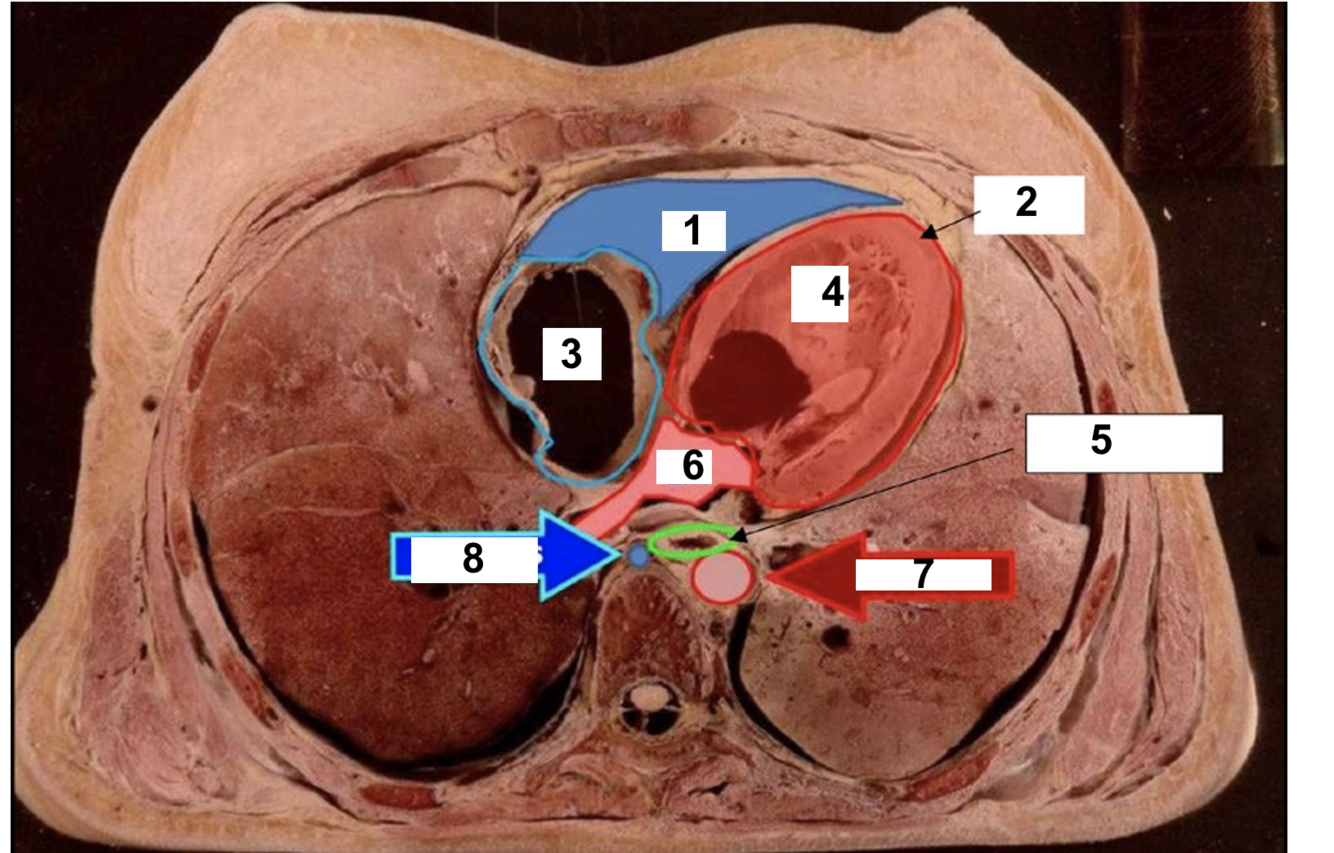

9

label

A

1. SA node

2. Inter-atrial pathways (bachmans bundle)

3. Internodal pathways

4. AV node

5. Bundle of HIS

6. RIGHT bundle branch

7. LEFT bundle branch

8. Purkinje fibres